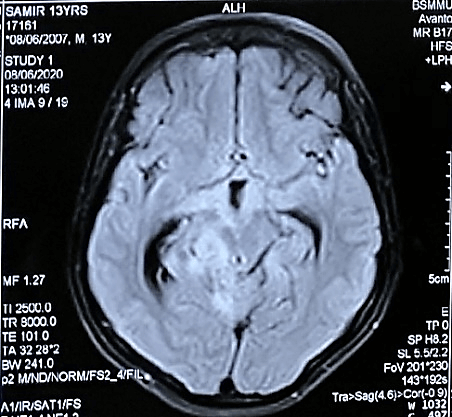

Figure 4: The lesions were also hyperintense in FLAIR images.

On the MRI T1-weighted images, multiple ill-defined mixed iso to slight hypointensity lesions were found to be located in basal, suprasellar, interpeduncular, prepontine, ambient and quadrigeminal cisterns (Figure 2) and the lesions became heterogeneously hyperintense on T2 WI (Figures 3A & 3B). The lesions were also hyperintense in FLAIR images (Figure 4) and after contract enhancement, there were multiple conglomerate ring shaped tuberculomas of 0.5 to 1cm size located at the basal, suprasellar and perimesencephalic cisterns and along the leptomeninges of basal region of cerebral hemisphere with racemose patterns. The central nonenhancing portions corresponded to caseation necrosis (Figures 5A & 5B). After treatment with antitubercular chemotherapy for 18 months the patient showed complete clinical recovery (Figure 6) but persisting radiological features of tuberculosis.